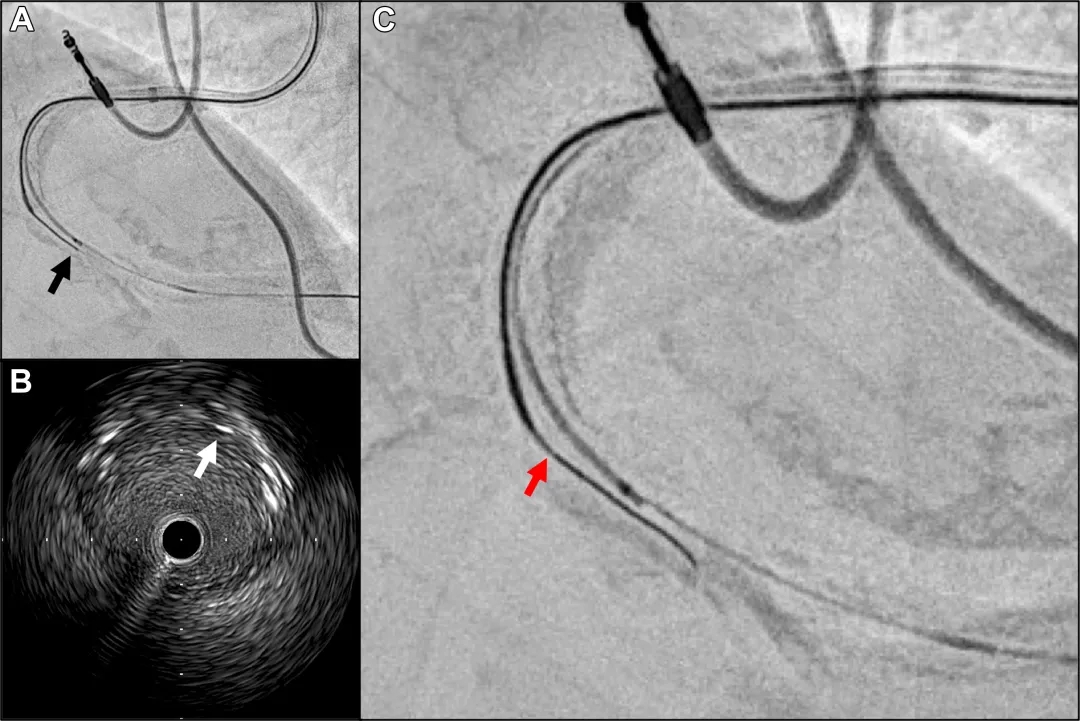

术者团队尝试穿刺钙化结节并置入另一根导丝,从钙化结节内部扩张病变。通过残余真腔的血管内超声清晰显示钙化结节近端起自既往支架远端边缘,在头端探测法实时IVUS引导下,微导管支撑下,Conquest Pro 12导丝头端(CP12ST,ASAHI INTECC)成功进入钙化结节(图3)。参考两个垂直角度的造影(图3A、3B),采用3D导丝技术主动操控CP12ST。IVUS显示CP12ST进入钙化结节后位于斑块内(图4A、4B),但未能从钙化结节重新进入残余真腔。虽然CP12ST位置接近残余真腔,但因病变阻力过大导致导丝受损,导丝不透光标记段出现分离(图4C)。为避免完全断裂,在微导管尽可能覆盖不透光标记段后撤出CP12ST。

图3 CP12ST穿刺钙化结节时的造影及IVUS图像

(A)左前斜位显示CP12ST穿刺位于IVUS图像左侧的钙化结节。

(B)右前斜/足位显示钙化结节位于IVUS图像右侧。

(C)CP12ST穿刺钙化结节时的IVUS图像(∗支架远端边缘;黄箭头指示CP12ST杆体;红箭头指示CP12ST头端)。

(D)图C的示意图。CP12ST在实时IVUS引导下穿刺钙化程度较低区域(∗支架远端边缘;黄箭头指示CP12ST杆体;红箭头指示CP12ST头端;白色区域为钙化结节表面;黑色区域为钙化结节)。

图4 CP12ST位于钙化结节内的冠状动脉造影及IVUS图像

(A)CP12ST头端位于刚过钙化结节的非钙化斑块内(黑箭头:CP12ST头端)。

(B)CP12ST杆体在IVUS图像中位于1点钟方向(白箭头:CP12ST杆体)。

(C)CP12ST不透光段存在轻微断裂(红箭头:CP12ST不透光段断裂处)。